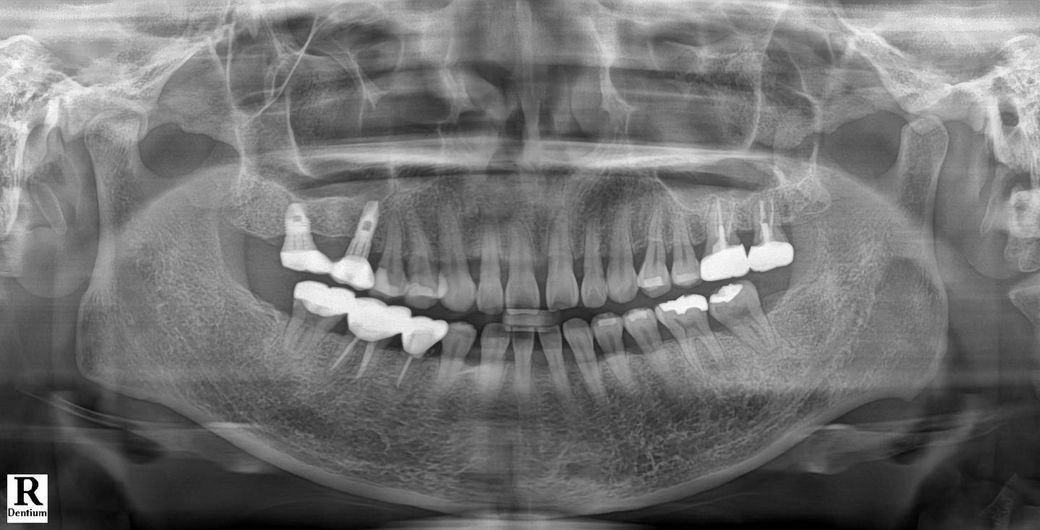

신경치료 15회만에 증상 없어져서 마무리 하고

크라운까지 완료 한지 2달이 지났어요!

1-2주 전부터 다시 뜨거운 것에 아프기 시작했어요

사진에서는 특별히 문제될 것은 없어보이며 지금 치과를 바꾼다고 나을지도 확신은 없습니다.

신경치료를 하면 일반적으로 통증이 없어져야지 정상적입니다. 통증이 생겼다는 것은 무언가 문제가 있다는 것입니다. 신경 치료하고도 해당부에 불편감이 있다면 치아에 가해지는 힘을 우선적으로 줄여보는 것을 권유드립니다.

그래도 불편감이 있다면 신경의 원인이 아닌 치아의 뿌리에 금이 갔을 수도 있습니다. 치아뿔이 근무했을 경우에는 치아를 발치해야 하는 경우도 발생할 수 있습니다. 자세한 확인을 위해서 치과에서 진료를 받아보는 것을 권유드립니다